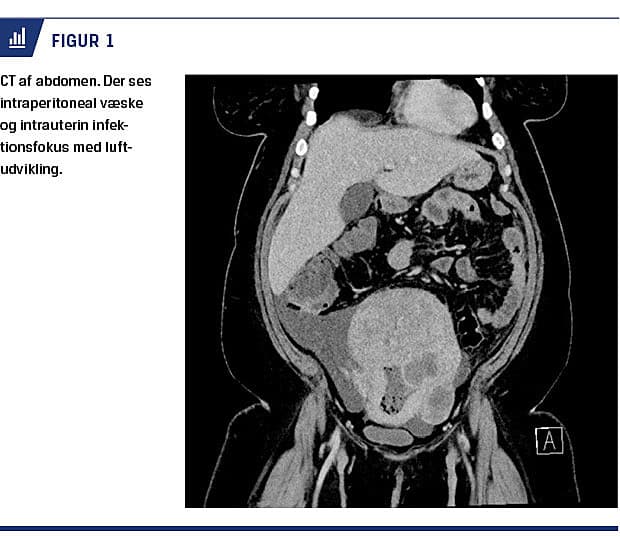

af laktatforhøjelse. Man afstod således fra diagnostisk laparoskopi og fortsatte med i.v.-givet antibiotisk behandling. Trods denne behandling fik patienten tiltagende abdominalsmerter om aftenen, hendes abdominalomfang tiltog, og hun var nu diffust direkte øm og slipøm i abdomen. Endvidere var hun blevet takykard og febril (puls 120 slag/min, temperatur 39,0 °C). CT’en blev gentaget; denne gang med fund af intrauterin luftudvikling og abscesdannelse (Figur 1). På mistanke om et intrauterint fokus for C. perfringens foretog et gynækologisk team på tredje døgn eksplorativ laparotomi med fund af svære nekroser og tegn til gasgangræn, hvorfor der blev udført total hysterektomi, bilateral salpingo-ooforektomi og appendektomi. Patologisvaret postoperativt påviste inflammation og nekroser, men ingen degenerative eller maligne forandringer i leiomyomet. Patientens kliniske tilstand blev langsomt bedre på kontinuerlig antibiotisk behandling, og hun kunne udskrives 11 dage postoperativt.